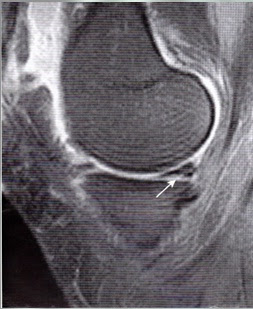

B.

Imagen FSE-DP sag de rodilla. Los parámetros de barrido utilizados en

esta imagen fueron idénticos a los utilizados en A, pero se obtuvo con

una bobina específica para la rodilla.

Obsérvese la importante mejora del índice señal-ruido y la representación de las estructuras anatómicas, comparado con A.